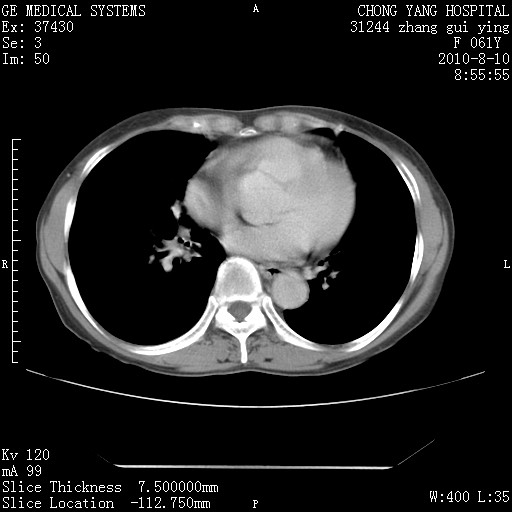

标题: CT28314:F61Y胸部增强,发热咳嗽一周入院,后面的为一周前平 [打印本页]

标题: CT28314:F61Y胸部增强,发热咳嗽一周入院,后面的为一周前平

右肺下叶中心性肺癌可能性大

1、支持考虑右侧中央型肺癌伴右肺中叶节段性不张及下叶支气管黏液痰栓    2、左肺上叶舌段感染。

支持右下肺中央型肺癌并左上肺感染.

我也觉得右肺中叶支气管受累

支持3楼意见,还要考虑:纵隔及肺门淋巴结转移、右侧少量胸腔积液。

确切的说:1:右肺下叶中心型肺癌侵及中叶支气管并中叶不张,纵膈淋巴结转移。2:左肺舌叶炎症。3:右侧胸腔少量积液

块影平扫32hu,动静脉期62-70hu.

1:右肺下叶中心型肺癌侵及中叶支气管并中叶不张,纵膈淋巴结转移。2:左肺舌叶炎症。3:右侧胸腔少量积液。支持!

右肺下叶内基底段近膈不规则肿块,考虑右肺下叶周围型肺癌可能性大。

考虑右下肺肺癌,纵隔淋巴结转移i。

右肺下叶中心型肺癌侵及中叶支气管并中叶不张,纵膈淋巴结转移。2:左肺舌叶炎症。3:右侧胸腔少量积液